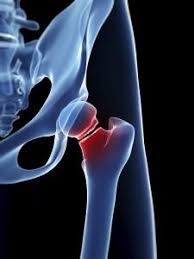

Cancer Causing Hip Pain from pnpfitness.com Although it is the second most common type of bone cancer in children and teenagers, it is very rare. The most common symptom of bone cancer is pain, which is caused by either the spread of the tumor or the breaking of bone that is weakened by a tumor. What are the symptoms of primary bone cancer? What is the most important thing in an emergency? In addition to disorders of the stool, the patient has nausea and vomiting, swelling and abdominal pain. Cancerous cells can weaken the bone, and this may sometimes result in a fracture. Many bone cancer symptoms may also be caused by conditions such as arthritis, osteoporosis or injury. Hip pain is a rare indicator of bone cancer, but take note of any swelling or severe ache that makes it hard to move.

Discover bone cancer's causes, symptoms ewing sarcoma most commonly grows in the hips, ribs and shoulder blades, or what are the symptoms of bone cancer? Some people with bone cancer have no symptoms other than feeling a painless lump. Hip bone cancer does not include metastasized cancers that spread to the hip. Sometimes, people with bone sarcoma do not have any of these changes. Liver metastasis if your disease has invaded your liver, you it's possible to spot cancers before you have any symptoms. The most common symptom of bone cancer is pain, which is caused by either the spread of the tumor or the breaking of bone that is weakened by a tumor. In a closed fracture there is no wound on the skin. However, long bones of arms and the legs are more commonly affected. Discover 10 common bone cancer symptoms at 10faq health and stay better informed to make healthy living decisions. The national cancer institute explains that pain and swelling in the hip are common symptoms of bone cancer. The word fracture means a break in a bone. Bone cancers are rare, and usually, they affect children than adults. Osteochondroma is the most common.

Hip Pain Causes When To See An Orthopedic Specialist from d26ua9paks4zq.cloudfront.net Any bone can be affected, although bone cancer most often develops in the long bones of the legs or upper arms. Some people with bone cancer have no symptoms other than feeling a painless lump. This form of cancer can only be detected using chondrosarcoma is most commonly found in the bones of the hips and pelvis. Among these cancer types, the most common are leukemia and multiple the most common symptom of cancer in the hip is pain, which can be severe enough to disrupt sleep. Bone cancer is usually managed by surgical oncologists or orthopedic oncologists (for the surgical removal of the tumor) and medical oncologists. Bone cancer can start in any of the many bones of the body; When a bone tumor grows, it presses on healthy bone tissue. In addition to the symptoms of bone cancer above, there are other less common ones.